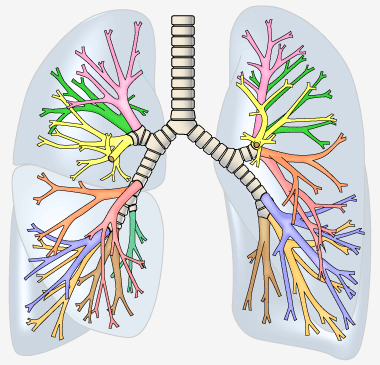

肺は、円錐形の器官で、空気が入っているのでスポンジのような感触の臓器です。肺は胸の左右に存在します。葉(よう)と呼ばれている部分に分かれています。葉とは肝臓、肺、乳腺、脳などの器官の部分を表す用語です。呼吸器系とは、呼吸に関連する器官のことです。これには鼻、喉頭(いんとう)、喉頭(こうとう)、気管、気管支、肺があります。 右肺には3つの葉があり、それぞれ上葉、中葉、下葉といいます。左肺は2つの葉を持っています。上葉、下葉です。右肺は左肺より少し大きいです。

右肺には10個の区域があり、左肺には9個の区域があり、合計で19個の区域です。

気管と気管支の解剖と役割

気管とは、吸い込んだ空気が口とのどを通り、肺へ入るため通路に当たる太い管です。気管支とは、気管が左右に分かれた後の管で、さらに枝分かれして肺胞という無数の小さな袋に達します。気管と気管支という通路を介して肺に空気を送ります。気管と気管支は呼吸器系の臓器の一つです。呼吸器系とは、呼吸に関連する器官のことです。これには鼻、咽頭、喉頭、気管、気管支、肺があります。

気管や気管支は、空気の流れ道であるとともに、粘液を分泌し、ほこりや細菌を捕らえます。この粘液は食道に飲み込まれるか、痰(たん)となって排出されます。